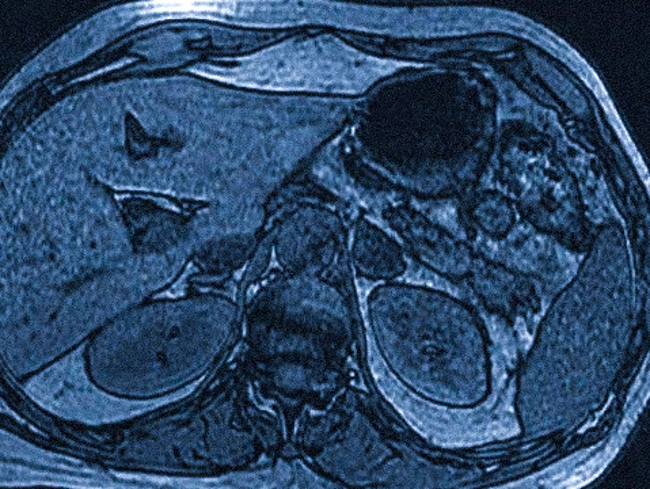

МР-сканирование с применением метода химического сдвига показывает поражение левой надпочечниковой железы.

Магнитно-резонансная томография (МРТ) предоставляет возможность различать рак и аденому, что делает её особенно ценным инструментом. Этот метод не предполагает лучевой нагрузки, что делает его наилучшим вариантом для диагностики у беременных женщин, детей и пациентов, которые уже получили радиотерапию.

На изображениях, полученных с помощью МРТ, можно заметить как количество, так и локализацию жировой ткани в новообразованиях печени, что является важным критерием при определении аденомы, кисты, миелолипомы и злокачественных опухолей.

В сложных случаях диагностики требуется применение комплексного подхода, включающего компьютерную томографию (КТ) с динамическим контрастированием и МРТ с использованием методики химического сдвига.